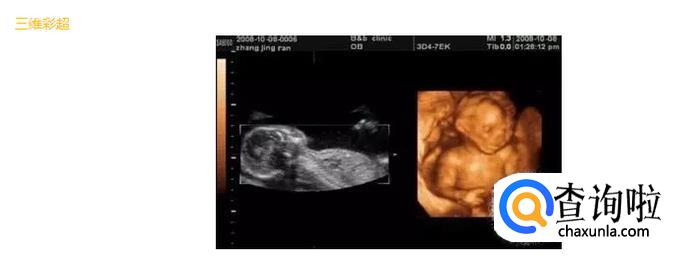

- 03

三维彩超就是将二维图像通过一个特殊的探头进行三维图像合成,透过屏幕可从各个方位观察胎宝宝。